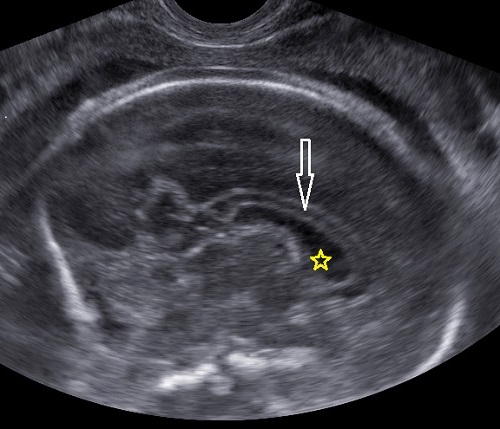

Las estructuras intracraneales después de la semana 18-20 del embarazo son muy características y permanecen visualmente invariables hasta el final del embarazo, solo modificando sus tamaños a medida que el feto crece. Esto es de gran ayuda ya que permite determinar la aparición de cambios que podrían sugerir desviación de la normalidad y aparición de una malformación congénita o lesión adquirida por eventos externos especialmente relacionados a infecciones y accidentes vasculares fetales.

Cuerpo calloso: es una estructura compuesta por haces nerviosos cuya función es la de conectar e integrar regiones corticales homólogas entre ambos hemisferios cerebrales. Su ausencia total puede conducir a problemas cognitivos y del desorrollo psicomotriz o pasar totalmente desapercibida. Su ausencia parcial, paradójicamente, se asocia con peor pronóstico. Como estructura ecográfica, es una de las más bellas que hay en el cerebro pero, para obtenerla se requiere pericia y muy buena resolución ecográfica. Sus alteraciones congénitas son diagnóstico de problemas primarios del desarrollo cerebral y se manifiestan con cambios indirectos en otras secciones cerebrales, especialmente ventriculomegalia.